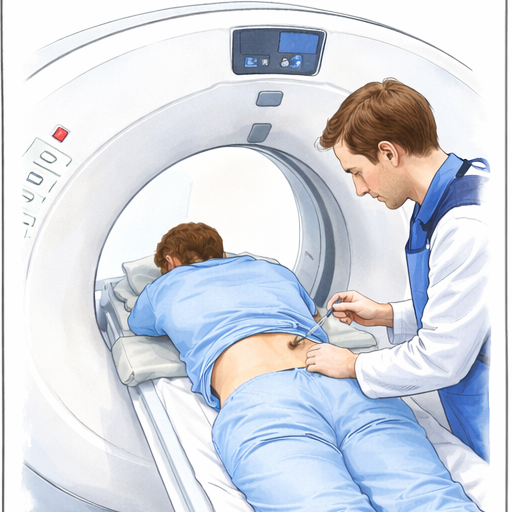

Präzise und schonende PRT-Behandlungen für gezielte Schmerzreduktion ohne großen Eingriff unter Sicht in "der Röhre" (DVT/CT)

Kompetente Orthopäden mit langjähriger Erfahrung in Bandscheibenbehandlungen führen täglich diese Eingriffe in unserem Hause durch.